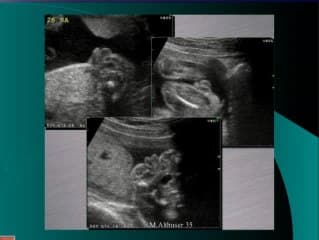

La médiathèque du Collège Français d'Échographie Fœtale (CFEF) constitue l'une des plus importantes collections de ressources vidéo dédiées à l'échographie fœtale en France. Avec plus de 3 261 vidéos, elle couvre l'ensemble des thématiques liées à la pratique échographique prénatale.

Vous y trouverez des conférences présentées lors des congrès nationaux et internationaux, des cours magistraux dispensés par des experts reconnus, des démonstrations pratiques sur des cas cliniques réels, ainsi que des podcasts et tables rondes sur les dernières avancées de la spécialité.